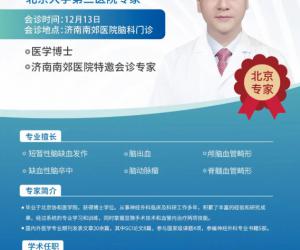

- 12-18北医三院脑科专家尹晓亮博士12月20日莅临南郊医院 疑难脑病会诊再启

- 12-11脑血管病患者福音!北大三院尹晓亮博士12月13日莅临济南南郊医院开展专家会诊

- 11-14好消息!北京脑科专家尹晓亮博士来济南南郊医院会诊啦!

- 11-11北医三院脑科专家尹晓亮博士加盟济南南郊医院 齐鲁百姓家门口享顶尖诊疗

- 11-08重磅官宣!北医三院尹晓亮博士加盟济南南郊医院守护脑健康

- 11-06北医三院脑科专家尹晓亮博士加盟南郊医院守护泉城百姓“脑健康”

- 12-18北医三院脑科专家尹晓亮博

- 12-11脑血管病患者福音!北大三